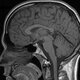

Ernst, realizó otra gran aportación a la RMN. Aplicando un tren de pulsos de radiofrecuencia. Ernst consiguió obtener espectros en dos dimensiones, donde las señales observadas eran consecuencia de la correlación del acoplamiento químico entre los núcleos de hidrógeno. Su trabajo fue el principio del desarrollo de la Resonancia Magnética de Imágenes(RMI). Ésta, aplicada en medicina se ha convertido en una herramienta muy útil de diagnóstico clínico no invasivo para un gran número de patologías

Paul Lauterbur, había desarrollado y aplicado un método de RMN para obtener imágenes bidimensionales y tridimensionales de objetos macroscópicos. El método se basaba en la aplicación de RMN de alta resolución con gradientes rotatorios de campo magnético para identificar secciones de volumen en estos objetos.